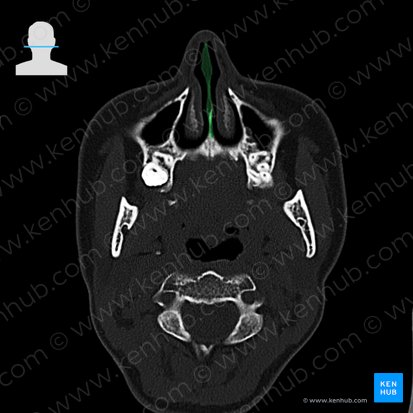

Die Nasenscheidewand, auch Nasenseptum genannt, ist die vertikale Trennwand in der Mitte der Nasenhöhle, die sie in eine linke und eine rechte Hälfte trennt. Sie besteht aus einem hinteren knöchernen und einem vorderen knorpeligen Abschnitt.

Der knöcherne Teil des Septums besteht aus zwei Knochen: der Lamina perpendicularis des Siebbeins (Os ethmoidale) oben und dem Pflugscharbein (Vomer) unten. Das Vomer artikuliert mit seinem oberen Rand am hinteren Ende mit der Lamina perpendicularis des Siebbeins. Diese geht nach oben in die Lamina cribrosa über.

Zwischen den beiden Knochen des Septums befindet sich vorne eine Lücke, die von einer Knorpelschicht, dem sogenannten Septumknorpel, ausgefüllt wird. Der Septumknorpel besteht aus hyalinem Knorpel und bildet den nicht verknöcherten Teil der senkrechten Platte des Siebbeins, der sich recht weit nach hinten zwischen den beiden Knochen erstrecken kann.

Struktur Knöcherner Anteil: Pflugscharbein (Vomer) und Lamina perpendicularis des Siebbeins (Os ethmoidale)

Knorpeliger Anteil: Cartilago septi nasi